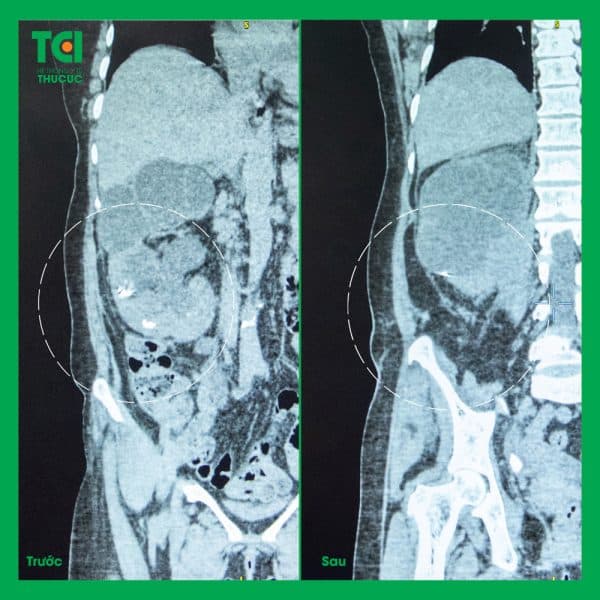

Bệnh nhân điều trị tán sỏi ngoài cơ thể tại Thu Cúc TCI